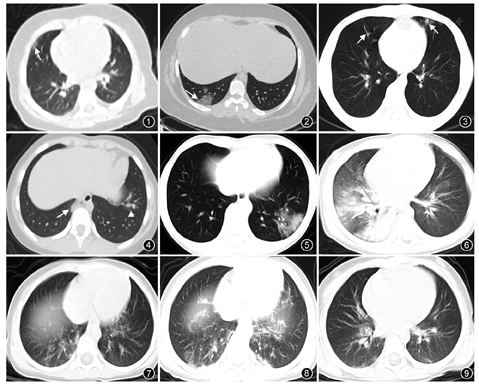

22例患儿中,3例(3/22)肺部CT正常,19例(19/22)肺部HRCT见病灶浸润,其中单侧肺病变7例,双侧肺病变12例。HRCT表现为:磨玻璃影6例,其中淡磨玻璃影4例、典型铺路石征磨玻璃影2例;4例呈肺实变改变,表现为局限性条索影、斑片状高密度影;6例表现为实变影与磨玻璃影共存,呈斑片状致密影夹杂周围磨玻璃影改变,其中1例呈右侧白肺表现;3例呈类支气管肺炎改变,表现为肺叶内散在点状或斑片状密度不均高密度影。下叶病灶较上叶为重,肺外后带较肺尖部、中央区多见。全部患儿均未见肺门淋巴结增大和胸腔积液,1例见叶间胸膜增厚。

病变累及单侧肺7例(7/19),左侧2例、右侧5例,仅累及单一肺段者4例、单叶多肺段1例、多叶多肺段2例;累及双肺12例(12/19),其中6例累及双肺下叶,2例病变位于双肺上叶,双肺下叶及左肺上叶受累2例,右肺中叶及左肺上叶受累1例,右肺中叶及左肺下叶受累1例。累及肺上叶11例(11/19),下叶16例(16/19),右肺中叶3例(3/19),上下叶均受累9例(9/19)。下叶病灶较上叶为重,肺外后带较肺尖部、中央区多见。

(1)磨玻璃影6例(6/19),均位于胸膜下,其中淡薄磨玻璃影4例,呈云雾状,形态不规则,较局限(图1);典型铺路石征磨玻璃影2例,密度稍高、较均匀、局限,铺路石征内见血管束及血管增粗影(图2)。(2)实变影4例(4/19),病变位于胸膜下,呈条索状、斑片状,范围局限、边界较清晰,与胸膜相连(图3)。(3)实变影与磨玻璃影共存6例(6/19),呈斑片状致密影夹杂周围磨玻璃影改变,其中5例实变影形态多样,呈楔形、不规则扇形、类圆形、片状或结节状等,病灶中间密度高、周围密度相对低,3例见典型晕征,2例见空气支气管征,1例见小叶间隔增厚(图4, 图5)。1例危重症患儿呈右侧白肺表现,表现为右肺弥漫性磨玻璃影与实变影,其中见空气支气管征(图6)。(4)类支气管肺炎改变3例(3/19),表现为单个肺叶内病变,沿支气管血管束走行的模糊影,从外向内带、向中央区延伸,边界模糊(图7)。所有患儿均无胸腔积液,均未见肺门淋巴结增大征象,1例患儿见叶间胸膜增厚。

儿童及成人COVID-19患者病变部位均多位于双肺外带胸膜下,病灶多发[4],但成人病灶分布更广泛、更弥漫[5],呈"反蝶翼征"多见,而儿童病灶都相对较局限,弥漫性分布相对少,"反蝶翼征"少见,磨玻璃影也不如成人典型,儿童病变较小,部分呈淡薄云雾状,典型铺路石征磨玻璃影在本组中仅占2例。类支气管肺炎改变也是儿童COVID-19的特点,本组3例,显示病变沿支气管血管束从外向内带走行,呈多个斑片状边界模糊影,如无家庭聚集性发病史易误诊为普通支气管肺炎。本组患儿均未见胸腔积液及肺门淋巴结肿大等征象。